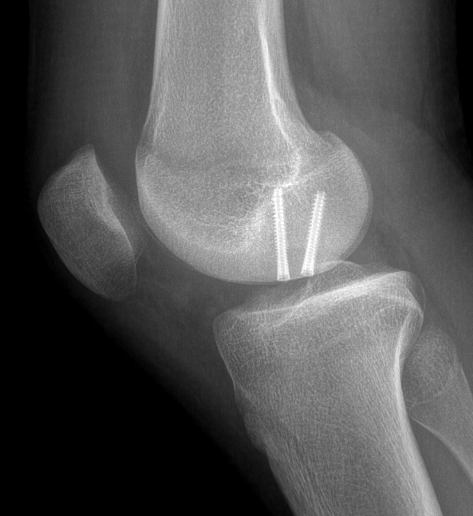

Medial femoral condyle

Technique

Arthroscope in lateral portal

Clear fat pad

Ensure can see entire dimensions of OCD

If fragment is displaced, reduce and pin with accessory K wire

Instrument and screw from accessory medial portal

- fragment is lateral aspect of the MFC

- typically need trans patella tendon portal to ensure correct trajectory

- ensure K wires centered in fragment

Flex and extend knee to place inferior / superior screws

- typically 2 - 3 screws maximum (3.5 mm)

- 22 - 26 mm long, want to stop short of growth plate

- ensure screw heads are buried under cartilage, but not too deep so they still engage fragment

- can microfracture with 1 mm k wire around screws

Inferior screw Superior screw